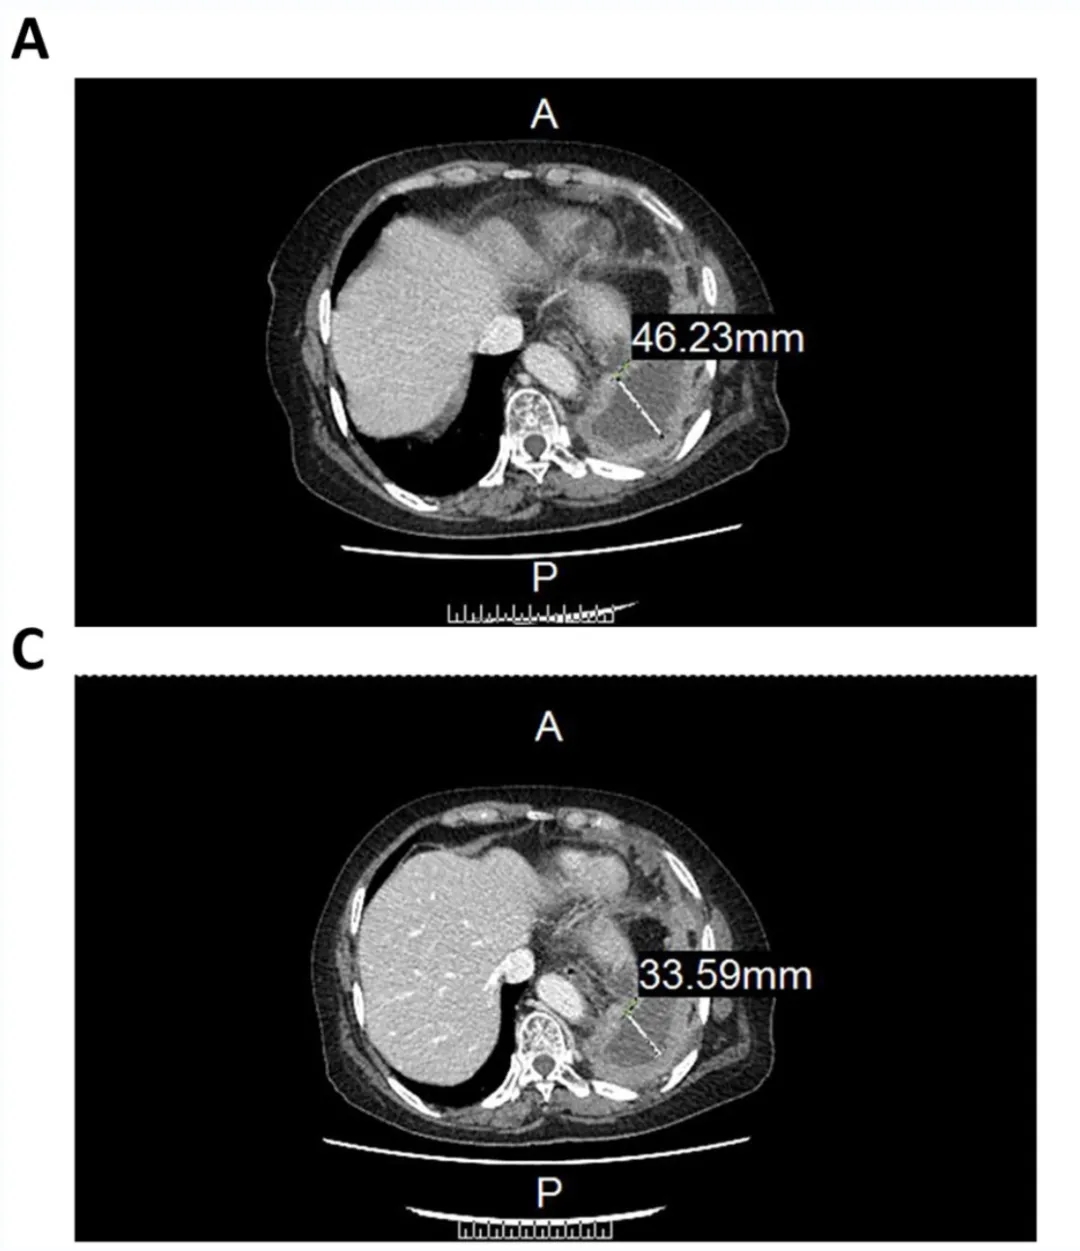

该患者经过3个周期的治疗后,CT图像显示,CCCR-NK92细胞疗法对肿瘤的治疗具有一定的疗效,具体如下。

1、该患者气管前-后腔静脉间质区的淋巴结,从11.3mm(毫米),减少至8.55mm(详见图B、D)。

▲图源“Sage Journals”,版权归原作者所有,如无意中侵犯了知识产权,请联系我们删除

2、左肺包裹的胸腔积液,从46.22mm(毫米)减少至33.59mm(图A、C)。